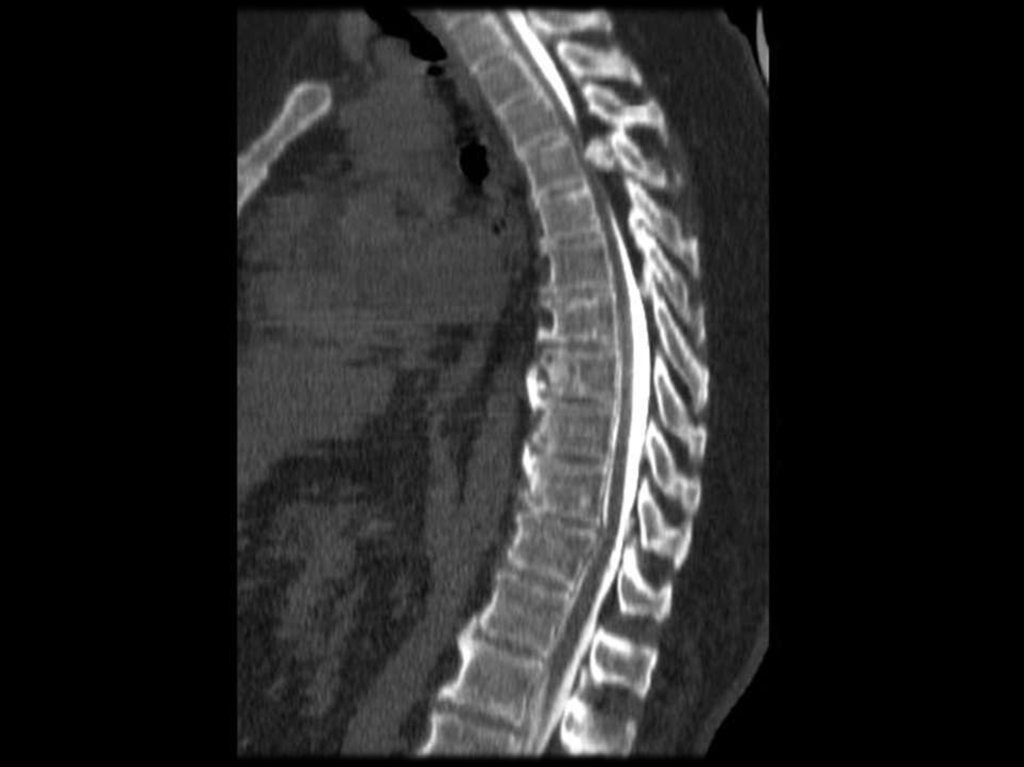

В грудном отделе – патология рёбернопозвонковых

суставов

с

формированием

артрозов. Поскольку грыжи выпадают в вогнутую

сторону, то в грудном отделе их наличие не

приводит к сдавлению спинного мозга.

В грудном отделе – патология рёберно-позвонковых

суставов с формированием артрозов. Поскольку грыжи

выпадают в вогнутую сторону, то в грудном отделе их

наличие не приводит к сдавлению спинного мозга.